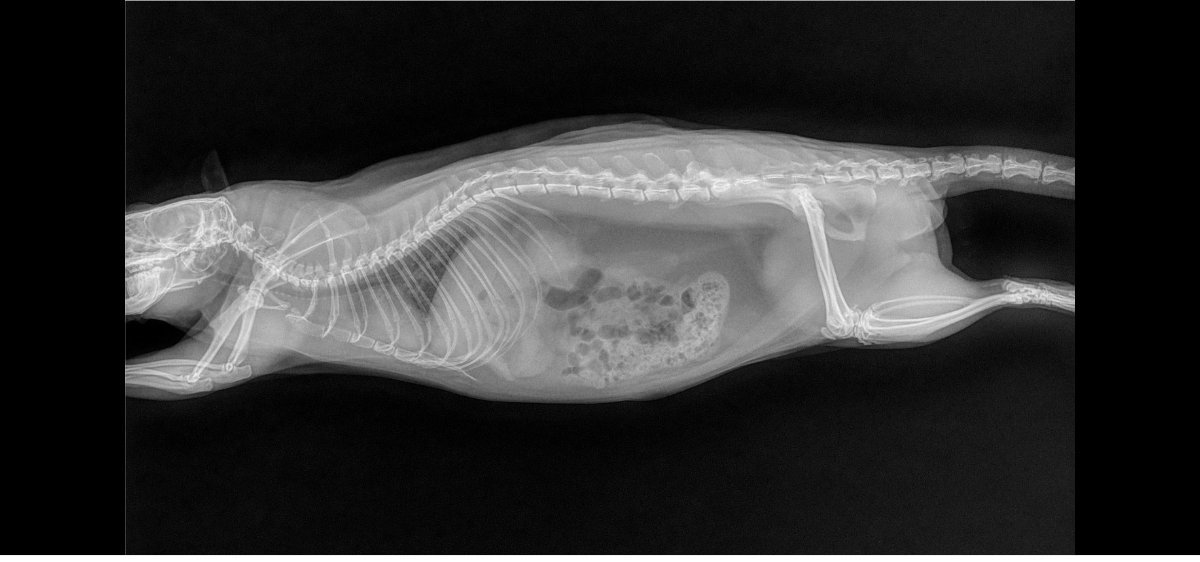

pas de super bonnes nouvelles car les deux miss ont les poumons atteints, si je m'en doutais un peu pour Izar qui ronflait depuis mars (c'est vite parti avec le collyre dans le nez) et respirait une peu trop vite, je suis tombée des nues pour Thari, qui me fait un coup à la Seren : zéro symptôme mais poumons pourris (si seulement elle pouvait avoir la même longévité :siffle:). Les deux pupuces sont donc sous deux antibiotiques (un par injection et un par voie orale) et Izar à en plus un AINS. Contrôle radio prévu dans quelques semaines.

Petites photos des belles et radios en spoil

Izar

Izarfaceavril2023.jpg.5285a5abdd7060aa126244520459ef3c.jpg

Izarprofildroitavril2023.jpg.31a414688eda128425e73b46a0b65f38.jpg

Izarprofilgaucheavril2023.jpg.0eec5561fec0efb202ff549e6a77de8f.jpg